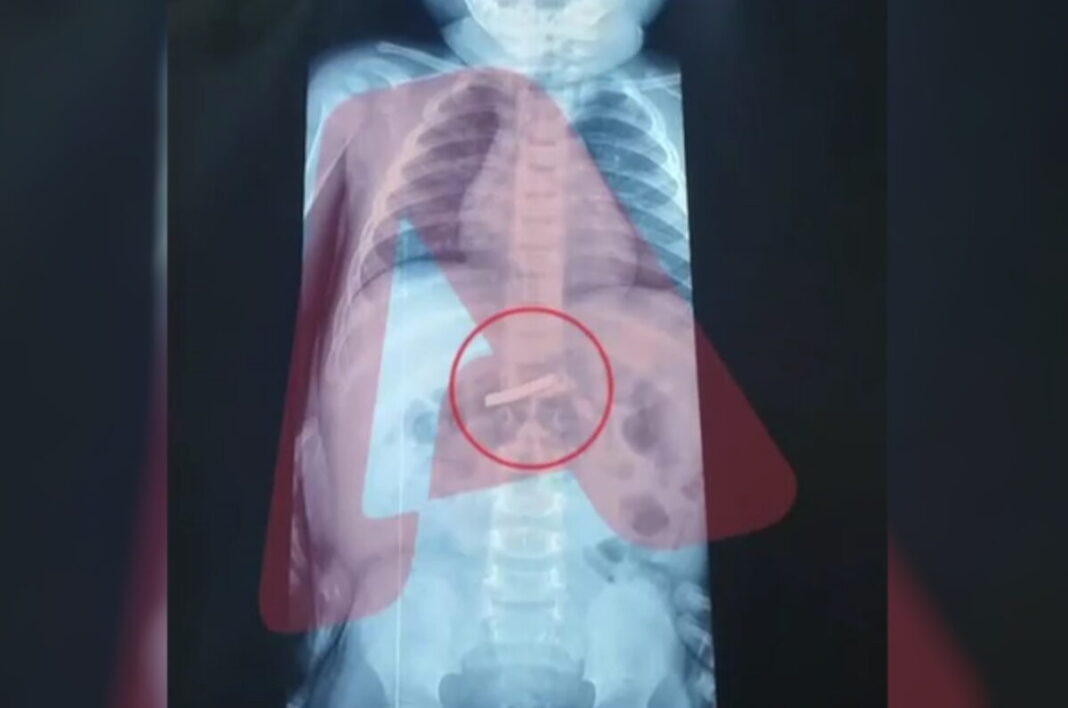

Ένας 3χρονος μεταφέρθηκε εσπευσμένα στο νοσοκομείο, το οποίο κατάπιε ένα ξυραφάκι. Το παιδί αφού έφτασε σε Παίδων της Αθήνας, υποβλήθηκε άμεσα σε ακτινογραφία, η οποία έδειξε ότι όντως υπήρχε το αιχμηρό αντικείμενο στο στομάχι του.

Όπως ενημέρωσαν οι γιατροί, τους γονείς του παιδιού, μετά την ακτινογραφία προσδιορίστηκε και το ακριβές σημείο όπου βρέθηκε το ξυραφάκι, ώστε οι χειρουργοί να προχωρήσουν σε επέμβαση αφαίρεσής του με ασφάλεια.